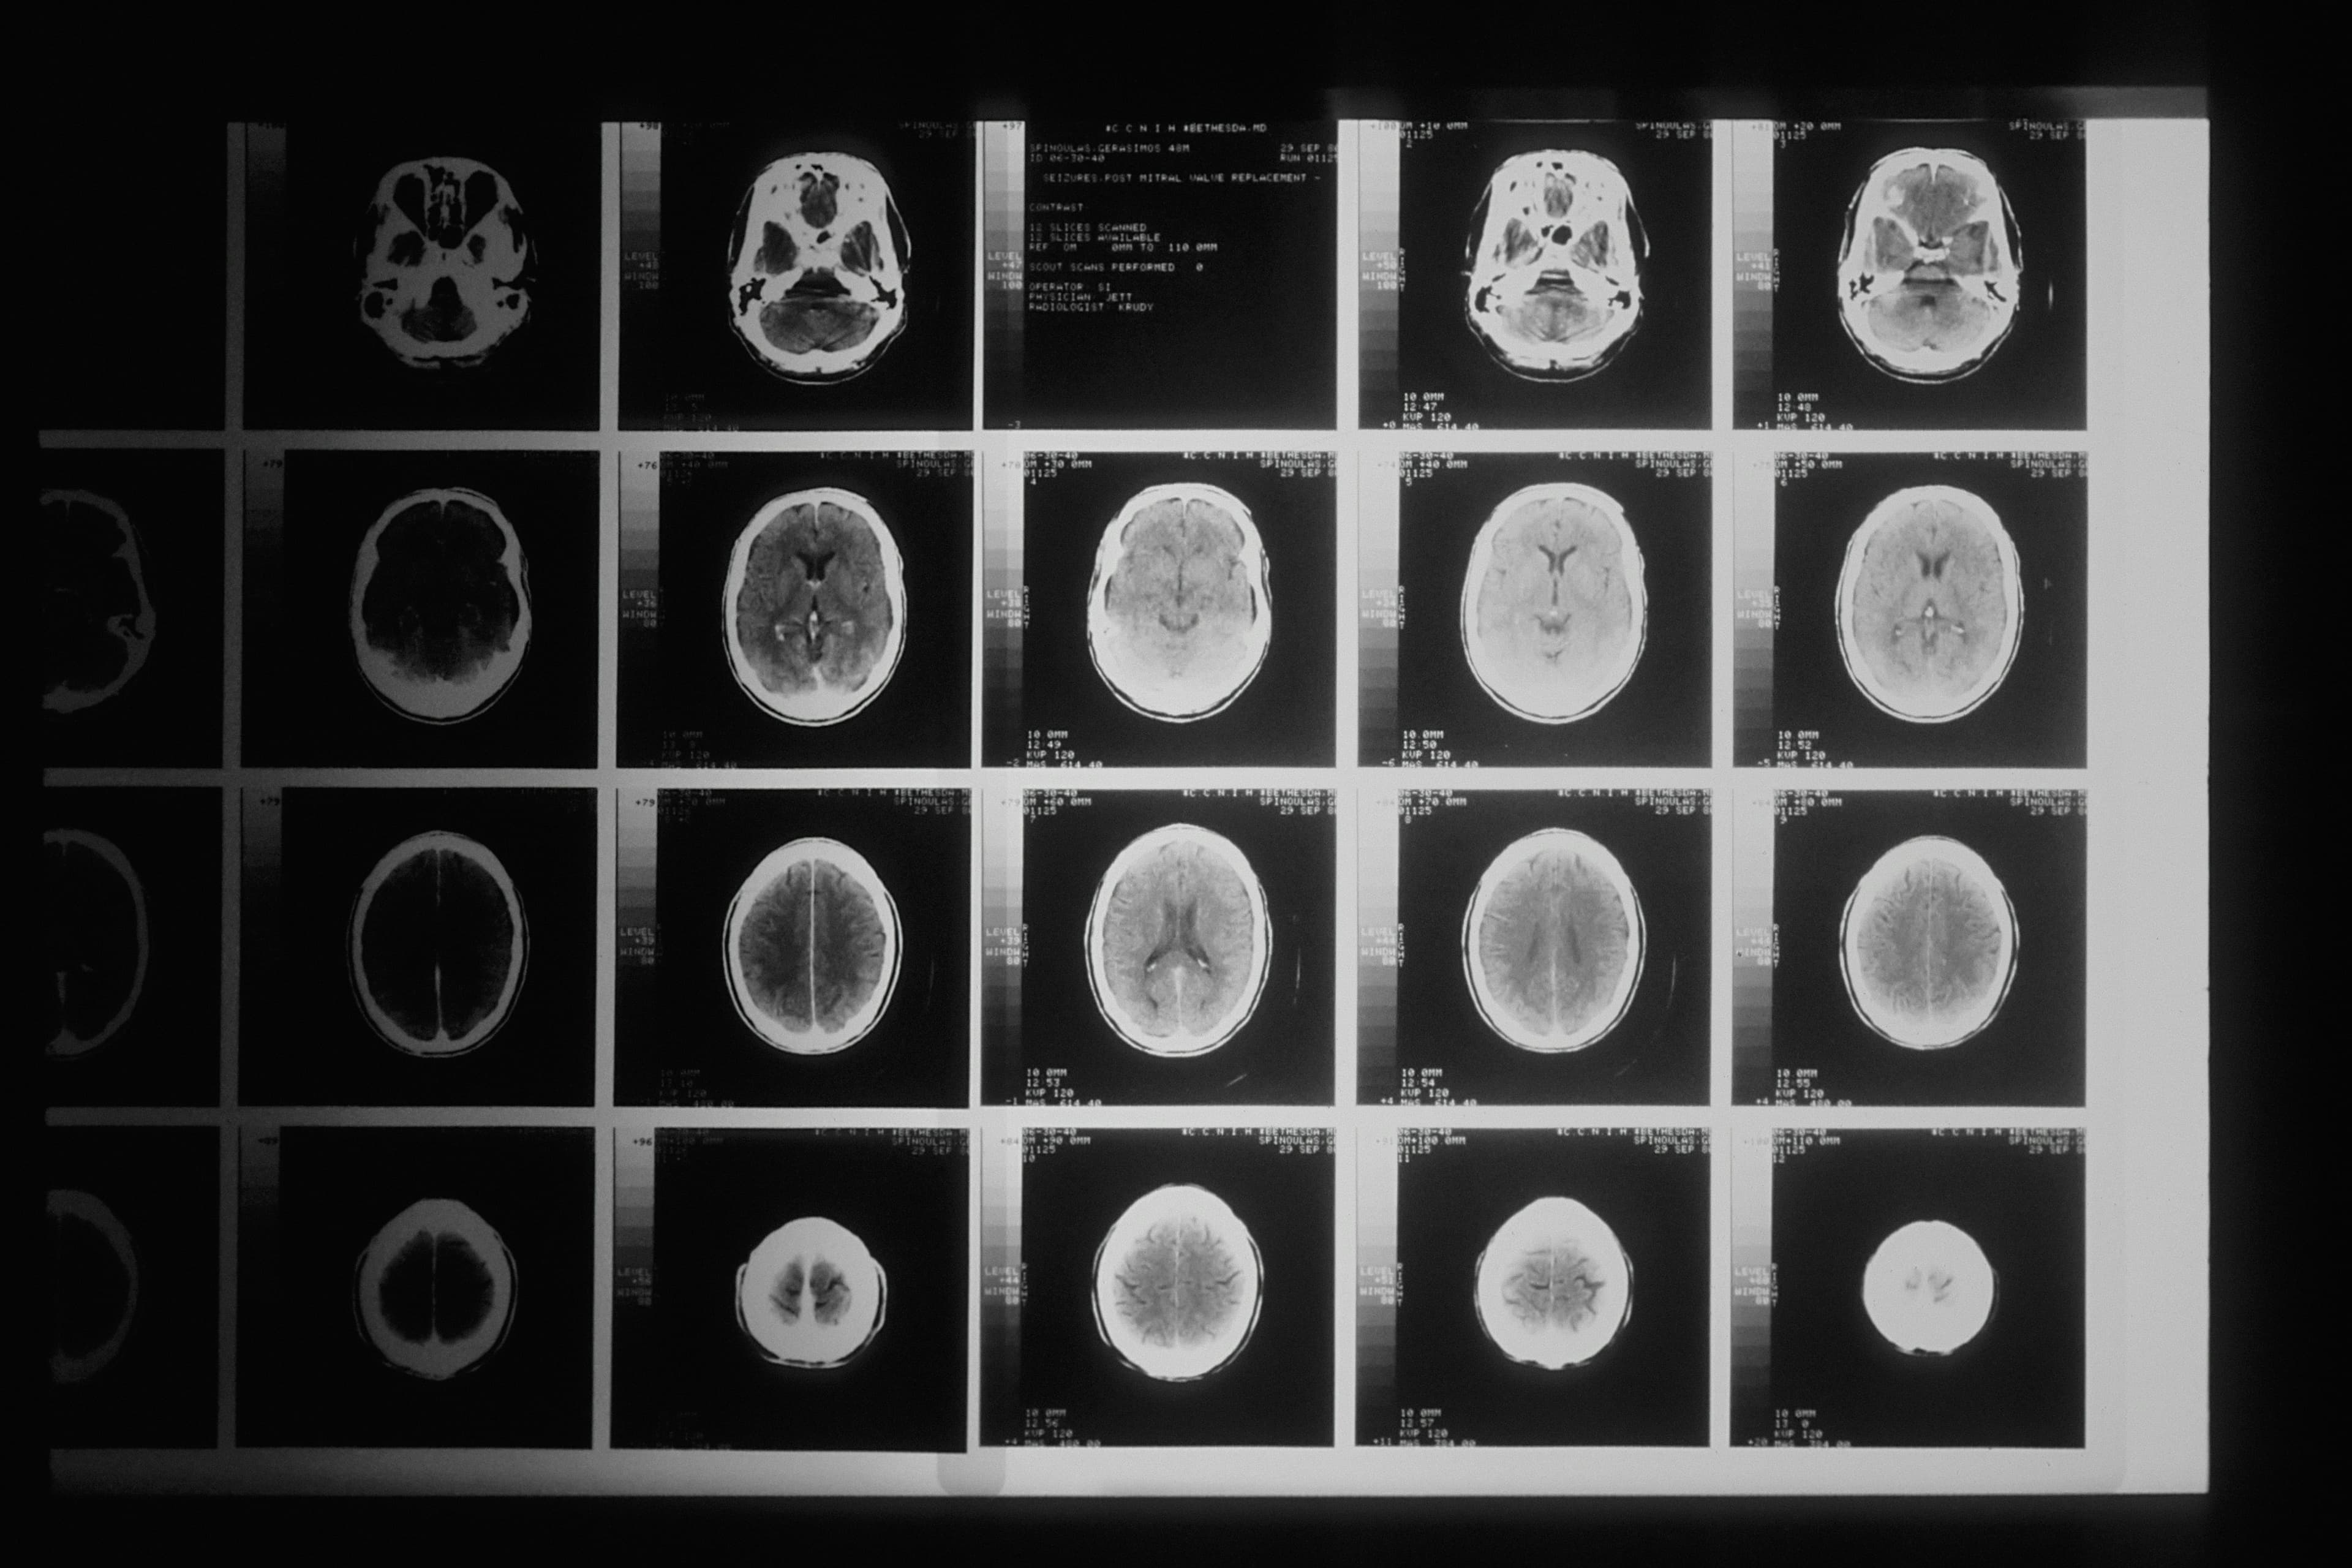

Brain Tumor Detection

This is a Deep learning model which uses Fast Mask R-CNN technique to capture the tumor cells in the evolution stage. The model is a YOLO model and been trained and tested using multiple algorithms. The model is integrated into an application so that the user can upload the MRI image in the application and it can identify the Tumor cells.